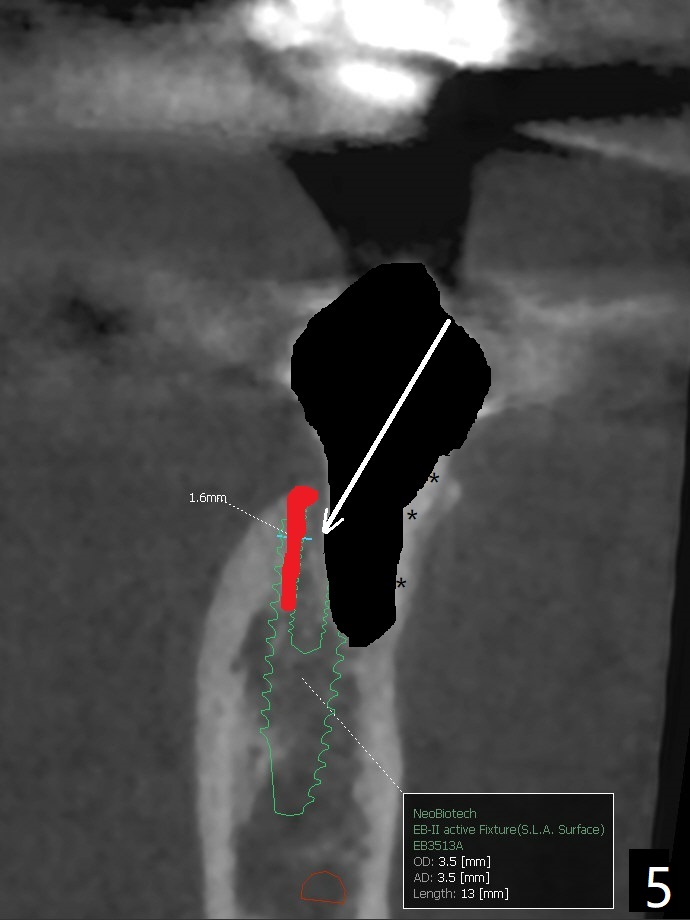

A 53-year-old woman develops an abscess lingual to the tooth #20 before #19 final restoration. Reanalysis of CT taken 5 months earlier shows the thin buccal plate (Fig.1 B). A 3.5x13 mm bone-level/3.5x17 mm tissue-level implant should be lingually placed (Fig.2,3). Socket shield will be performed (Fig.4 *); the lingual cortex removed with Lindamann bur (red) for ~1.6 mm. Initial osteotomy will be conducted in the lingual wall of the socket coronally (Fig.5 white arrow); after penetration, the initial drill will change the trajectory (Fig.6).